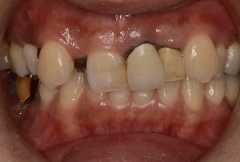

部分矯正とインプラントを組み合わせた治療例

1−5.部分矯正とセラミックで期間を短縮できるハイブリット矯正

歯を失っている部分や被せてある歯を利用して、部分矯正とセラミック治療を一緒に行う方法です。歯の移動距離を小さくすることによって歯や歯茎へのダメージを少なくします。またセラミック治療を行うことで噛み合わせを治すこともできます。歯や歯茎の負担が軽いために大人の方には特におすすめの治療法です。